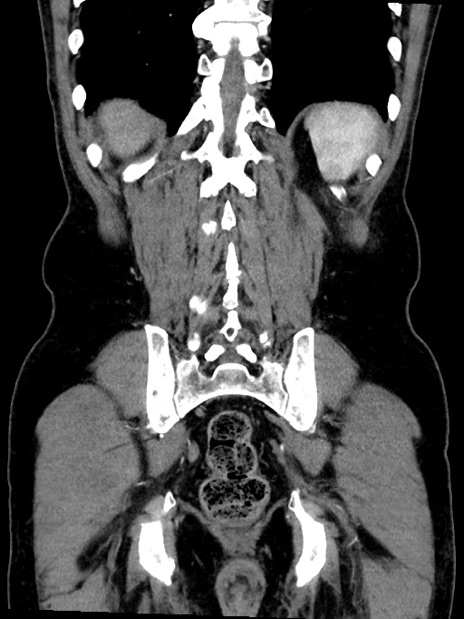

横断像

【症例】70歳代 男性

【主訴】腹部膨満、嘔吐

【現病歴】昨日より腹部膨満感出現。本日増悪し、仙痛出現。嘔吐あり、受診。

【既往歴】糖尿病、胆摘後

【身体所見】BP 149/80mmHg、HR 74/min、BT 35.9℃、腹部:膨満、軟、圧痛なし。腸雑音減弱あり。上腹部正中切開瘢痕あり。

【データ】WBC 13500、CRP 1.72